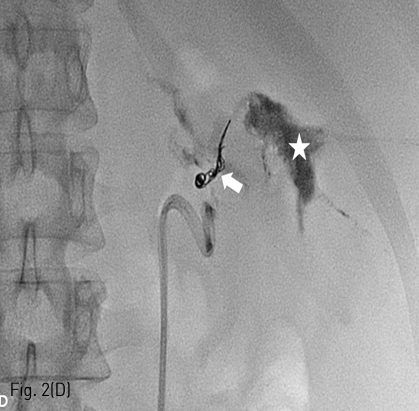

Fig 2D

(D) Spot radiograph obtained after successful embolization procedure shows complete occlusion of urinary fistulous tract by multiple coils (arrow) and obliteration of urinoma cavity (star) by glue cast.